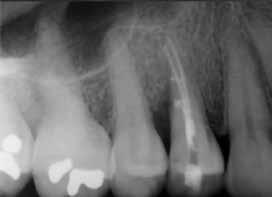

Krell és Caplan kutatásában 2086 repedt fogat vizsgáltak meg. A vizsgált fogak között leggyakrabban a második alsó nagyőrlőfogak (36%), majd ezt követően az első alsó nagyőrlők (27%), és végül az első felső nagyőrlők (18%) fordultak elő. A kutatási eredményeik szerint a fogbél állapota nem befolyásolta jelentős mértékben a kezelés várható kimenetelét. (Irreverzibilis pulpitis 85%; necrosis 80%; korábban gyökérkezelt 74%). A kimenetel szempontjából ugyanígy indifferens volt a páciensek neme, életkora, a kezelés időpontja, a fog pozíciója, a fog helyreállítása során használt anyag típusa, valamint az érintett fogfelszínek száma. 2014 júliusában egy 45 éves hölgy páciens azzal a panasszal kereste fel a rendelőnket, hogy nagyjából 10 napja egy fájdalmas duzzanat alakult ki a jobb felső első kisőrlője koronája mellett (14). A klinikai vizsgálat során egy amalgámtömést találtunk a panaszos fogban. A tömés széli zárása nem volt megfelelő, a disztális záróléc és a tömés között rést tapasztaltunk. A fog disztobukkális és linguális felszíne mellett 8 mm-es csontos tasakokat mértünk. A periapikális felvételen az 14-es foggyökér disztális felszínének megfelelően vertikális irányú radiolucens felritkulást észleltünk. A klinikai vizsgálat során a mesiális zárólécet kettéválasztó törésvonalat detektáltunk (17–18. ábra). A fogszenzibilitás vizsgálata során negatív eredményt kaptunk. A páciensnek ismertettük az elérhető terápiás lehetőségeket: 1, a 14-es fog eltávolítása, majd a foghiány 3 tagú cementezett híddal történő pótlása; 2, a 14-es fog eltávolítása, kemény- és lágyszöveti augmentáció, majd implantátum behelyezése; 3, a 14-es fog gyökérkezelése, gyökértömése és ezt követően a csücsökborítást biztosító restaurátum készítése. Arra is felhívtuk a páciens figyelmét, hogy a 3. terápiás lehetőség választása esetén nem tudjuk a fogmegtartás sikerességét garantálni, de végül – főként anyagi okok miatt – mégis ezt a terápiás opciót választotta. Fontos megjegyezni, hogy a repedt fogak ellátási lehetőségeit a törésvonal mélysége, elhelyezkedése, lefutása nagyban befolyásolja. A kezelés megtervezése során a fog és a fogat körülvevő szövetek állapotával kapcsolatos számtalan különböző faktort kell egyidejűleg figyelembe vennünk. A gyökérkezelést követően a gyökértömést meleg vertikális kondenzációs technikai alkalmazásával készítettük el (19. ábra). A hozzáférési nyílást folyékony és hibrid kompozit tömőanyag segítségével zártuk. A zárás elkészítése során a dr. David Clark által kifejlesztett Bioclear matricarendszert alkalmaztuk. A 6 éves kontroll során készített (2020) röntgenfelvételen a csontos defektus telődése volt megfigyelhető. Ez is a parodontális defektus gyógyulását igazolta (20–21. ábra).

17. ábra: A 14-es fog gyökerének disztális felszíne mellett vertikális csontpusztulásra utaló jelek észlelhetőek. Klinikailag ezen a területen 8 mm mélységű tasakmélységet mértünk. – 18. ábra: A 14-es fog disztális zárólécének megfelelően törésvonal észlelhető, ugyanakkor a csücskök teljes szeparálódására utaló jelek nem láthatóak. Az amalgámtömés eltávolítását követően jól megfigyelhető volt a törésvonal teljes lefutása. – 19. ábra: A gyökértömés elkészítése során meleg vertikális kondenzációs technikát alkalmaztunk. A felvételeken oldalcsatornák jelenlétére utaló jelek is észlelhetőek. – 20–21. ábra: A 2020-ban készült kontrollfelvételeken jól látható a csontos defektus telődése. A radiológiai jelek alapján (jól lekövethető gyökérhártyarés) a parodontális ligamentumok regenerációját is vélelmezzük.